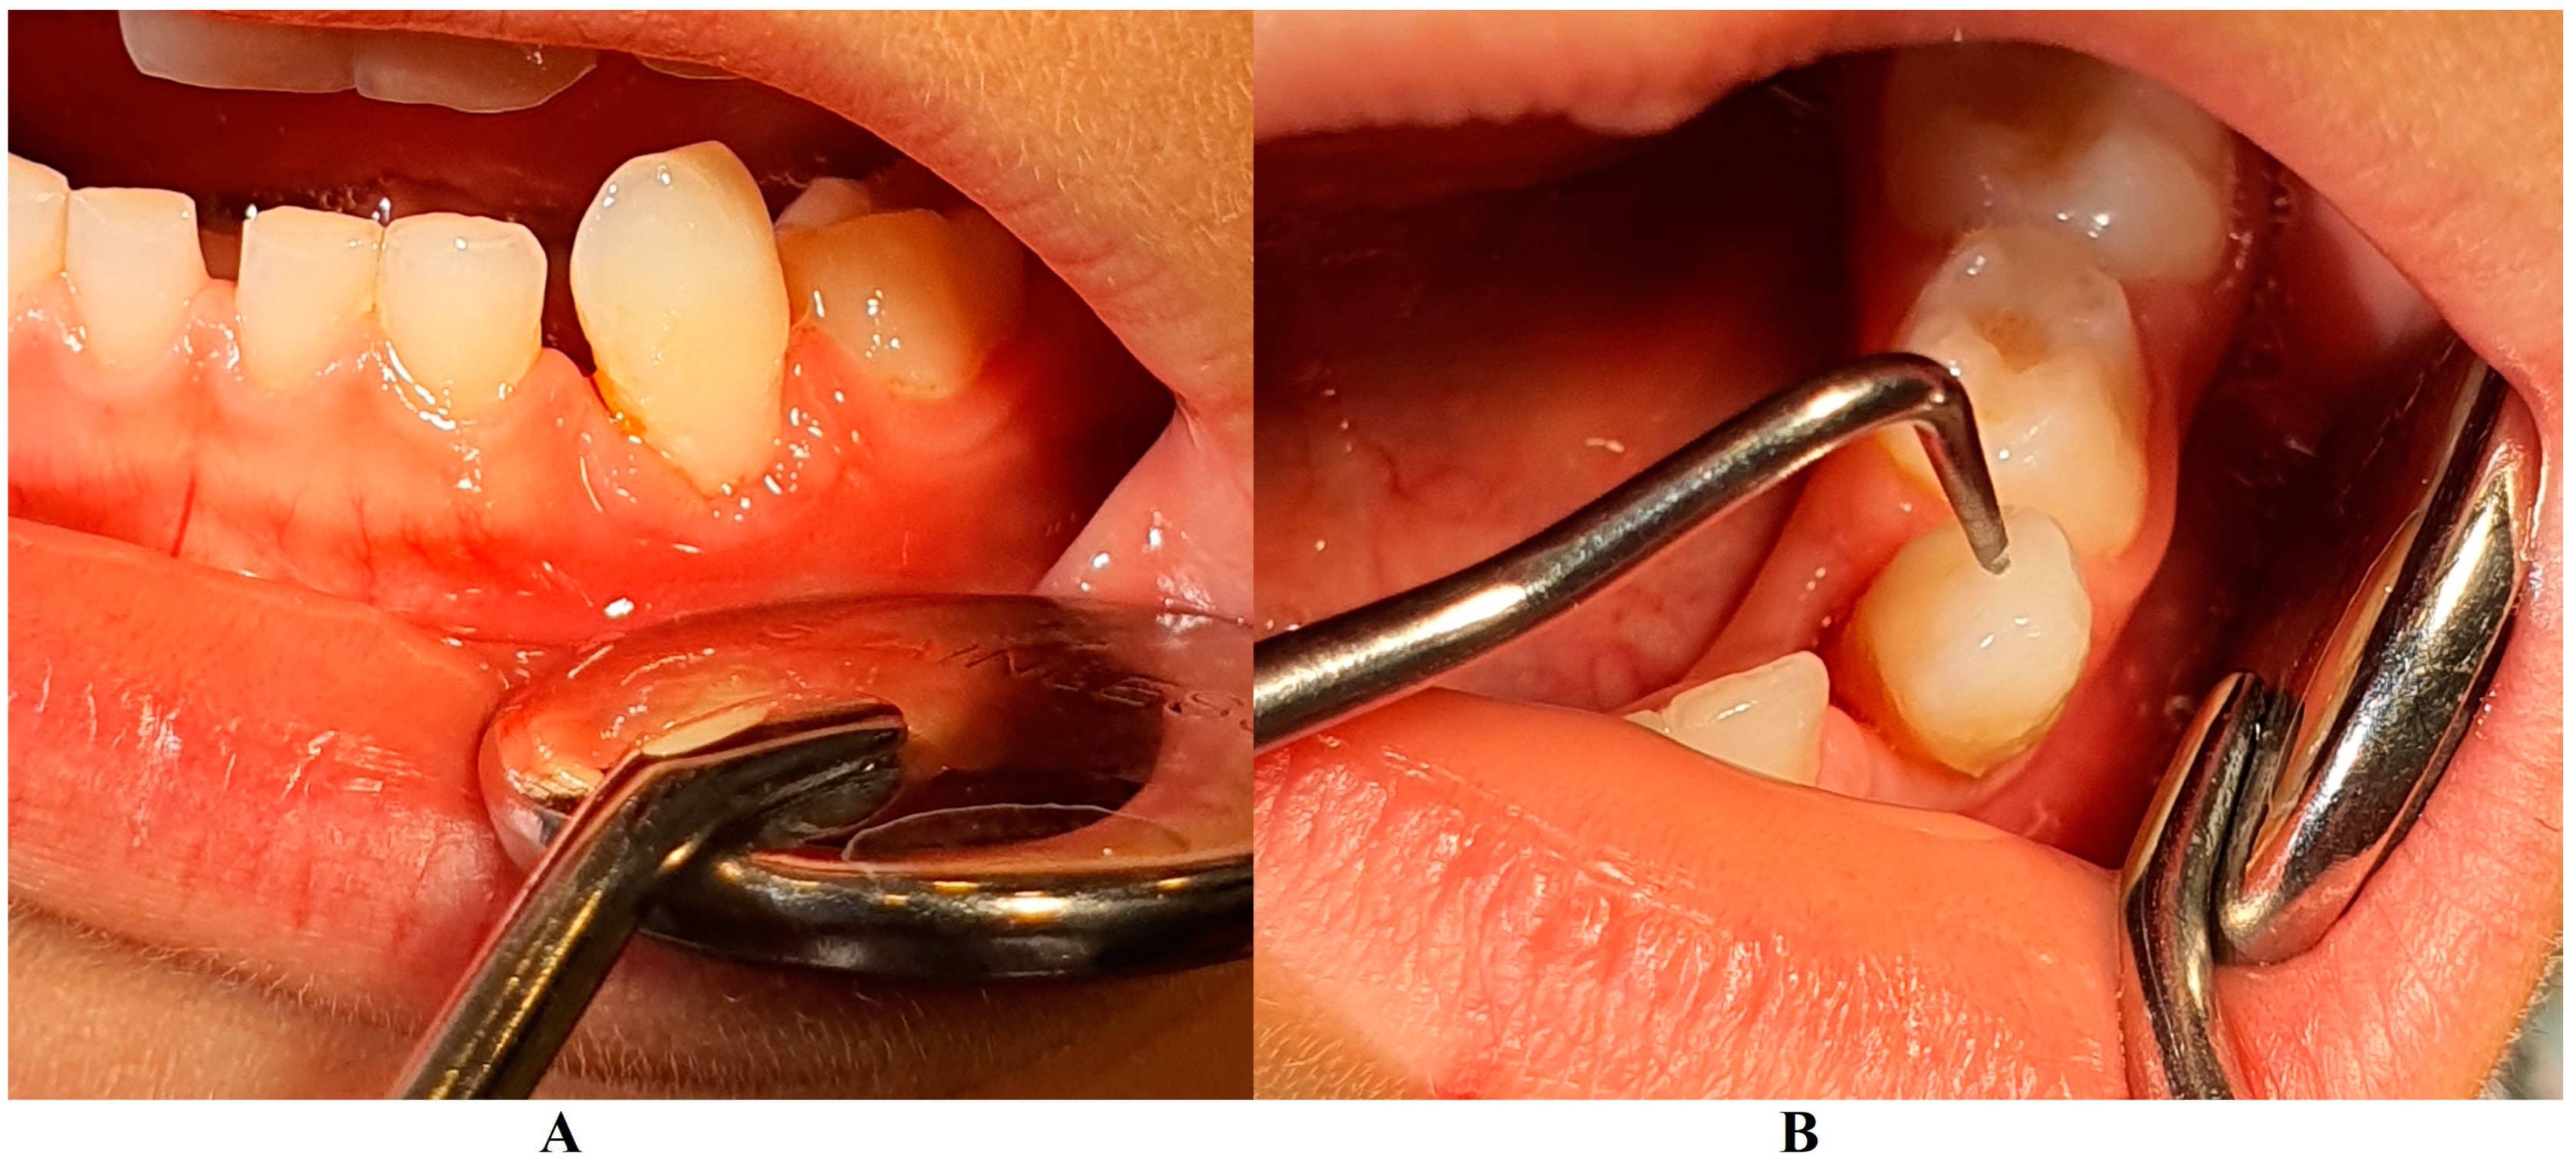

The family spent the summer holidays in Klausenburg/Cluj-Napoca (Romania), where they consulted another dentist (2 August), since tooth movements increased, and they were concerned about the outcome. After the clinical examination and review of previously available radiographs, blood tests, and the patient’s clinical history, a diagnosis of Stage IV grade C localized periodontitis/LPP was established (hypophosphatasia/hyperphosphatasia was excluded from the beginning, despite the fact that genetic test results were not yet available) (Figure 2 and Figure 3). These two figures show the case in early August, with a localized hyper-eruption of the tooth due to extended periodontal loss, inflammation in periodontal pocket, and hyper-immune response. We must emphasize that till early August, no visible signs of orthodontic problems (e.g., hyper-eruption) were found after multiple clinical examinations. The earlier X-ray examination (from early June, Figure 1) was taken into consideration when the diagnosis of Stage IV grade C localized periodontitis/LPP was formulated. To confirm the laboratory diagnosis and identify the type of bacteria involved, a periodontal pocket bacterial test sample was taken (laboratory confirmation, 3 August), and in the meantime, professional oral hygiene and an adjuvant topical combination of amoxicillin and metronidazole was applied for a period of 10 days (due to advanced surrounding bone loss). The periodontal bacteria pocket test came positive, with increased levels of Fusobacterium nucleatum/periodonticum and Capnocytophaga spp. (16 August) confirming the Stage IV grade C localized periodontitis/LPP diagnosis. Because the tooth movement was significant by the time of LPP diagnosis due to advanced periodontal support loss, the tooth was lost at the beginning of September (Figure 4).

Figure 3.

(A)—Gingival inflammation, (B)—advanced tooth mobility, which led to the LPP diagnosis (details, in early August).

On the other hand, when the first Stage IV grade C localized periodontitis/LPP diagnosis was established (2 August), the clinical examination showed an increased mobility of the temporary lower left canine due to massive bone and periodontal ligament loss, associated with a localized inflammation of the free gingival margin around the tooth, and with small amounts of dental plaque due to difficulties with oral hygiene (Figure 2 and Figure 3). No other plaque deposits, inflamed gingiva, or teeth mobility issues were detected during the clinical examination. When this information was correlated with the radiological examination from two months prior (19 June, Figure 1), with localized bone loss, the diagnosis based on clinical and radiological data was confirmed, with no need for further radiological examination. Moreover, the blood test with higher levels of lymphocytes [2,14] also confirmed Stage IV grade C localized periodontitis/LPP diagnosis. To assess the periodontal pocket bacteria responsible for this atypical LPP case (i.e., temporary molars/incisors are usually involved [1,2,10], rather than the canine, as in this case), a canine periodontal sulcus secretion test was sampled and sent to the laboratory.

A rapid Stage IV grade C localized periodontitis/LPP diagnosis is essential, since the aggressive auto-immune response to bacteria can rapidly lead to a resorptive process [1,2,3,4,5,6,7,8,9,11]. Thus, a simple bacterial test to identify the pathogenic bacterium types would provide both diagnostic confirmation and justification for antibiotic treatment [2,3,11,12,13,14,15]. If LPP disorder is identified early, there is time to wait (i.e., usually up to two weeks) for lab test results, and only then should antibiotic therapy proceed [5,6,9,10,16,17,18]. However, if the LPP diagnosis is late (as it was herein), antibiotic treatment must be started, with a combination of two large-spectrum antibiotics (amoxicillin and metronidazole) to cover most bacterial types [5,6,9,10,16,17,18]. It must be emphasized that LPP usually comes without or with very few plaque deposits (as the case herein showed—see Figure 1, Figure 2, Figure 3 and Figure 4), with little influence over surrounding gingival inflammation [1,2,4,5,6,7,8,9,10].